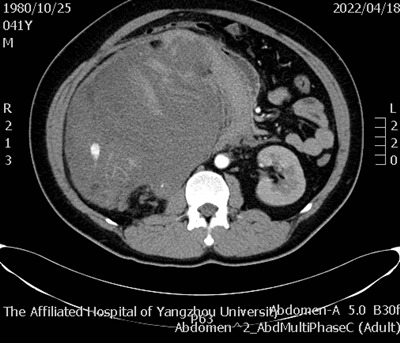

4月22日晚间,在麻醉科和手术室的紧密协助下,诊疗团队对患者进行了右肾肿瘤根治性切除术+腹膜后血肿清除术,由于术前合并症多,导致手术难度较大、术中出血多,但在医生娴熟的技术下,手术顺利完成。术后经重症医学科精心治疗,患者已顺利脱机,无十二指肠及周围脏器损伤,目前恢复良好。

术后腹部CT平扫_副本.png